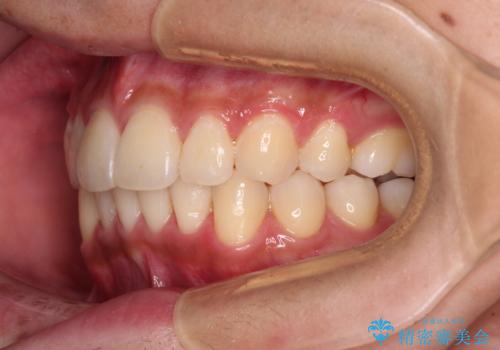

矯正治療の後戻りをインビザライン・ライトで解消

- 矯正治療の後戻りを気にして来院された患者様です。

後戻りは軽微であったので、インビザライン・ライトにより矯正治療を行うこととしました。

インビザライン・ライトは提供されるマウスピースの数に制限があり、通常のタイプよりもマウスピース提供期間が短くなっている一方、安価に治療を行うことができるプランです。

治療のゴールも変更できないため、軽微な歯列不正や、後戻り改善などに適しています。